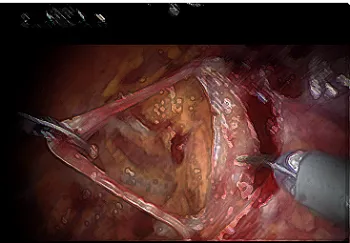

Previous studies have shown favorable results with respect to urinary control when placing a sling at the time of open radical prostatectomy, when the prostate is removed through an open incision from the pubic bone to the belly button. However, this has never been recreated in patients undergoing removal of their prostate with robot assisted laparoscopic surgery. UCSF urologists have published their preliminary results, which suggest the sling may help in improving recovery of urinary control, without causing any adverse effects. However, further testing is required to confirm a benefit of the sling in improving continence. The technique involves use of the vans deferens to act as the sling. The vans deferens is a tube that carries sperm from the testis to the prostate. This tube is no longer needed once the prostate is removed. Skilled surgeons “harvest” the vans deferens and attach to support to the urethra and bladder neck.